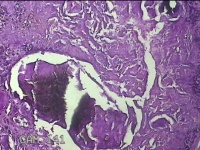

左外踝包块

性别

男

年龄

31岁

临床诊断

皮下结节

一般病史

发现左外踝包块1年余。

标本名称

大体所见

灰白暗红色包块1.8x1.3x0.7cm一个,表面糜烂,切开包块,内见大量石灰样物,内壁粗糙。

去了解病史,应该是痛风结节。